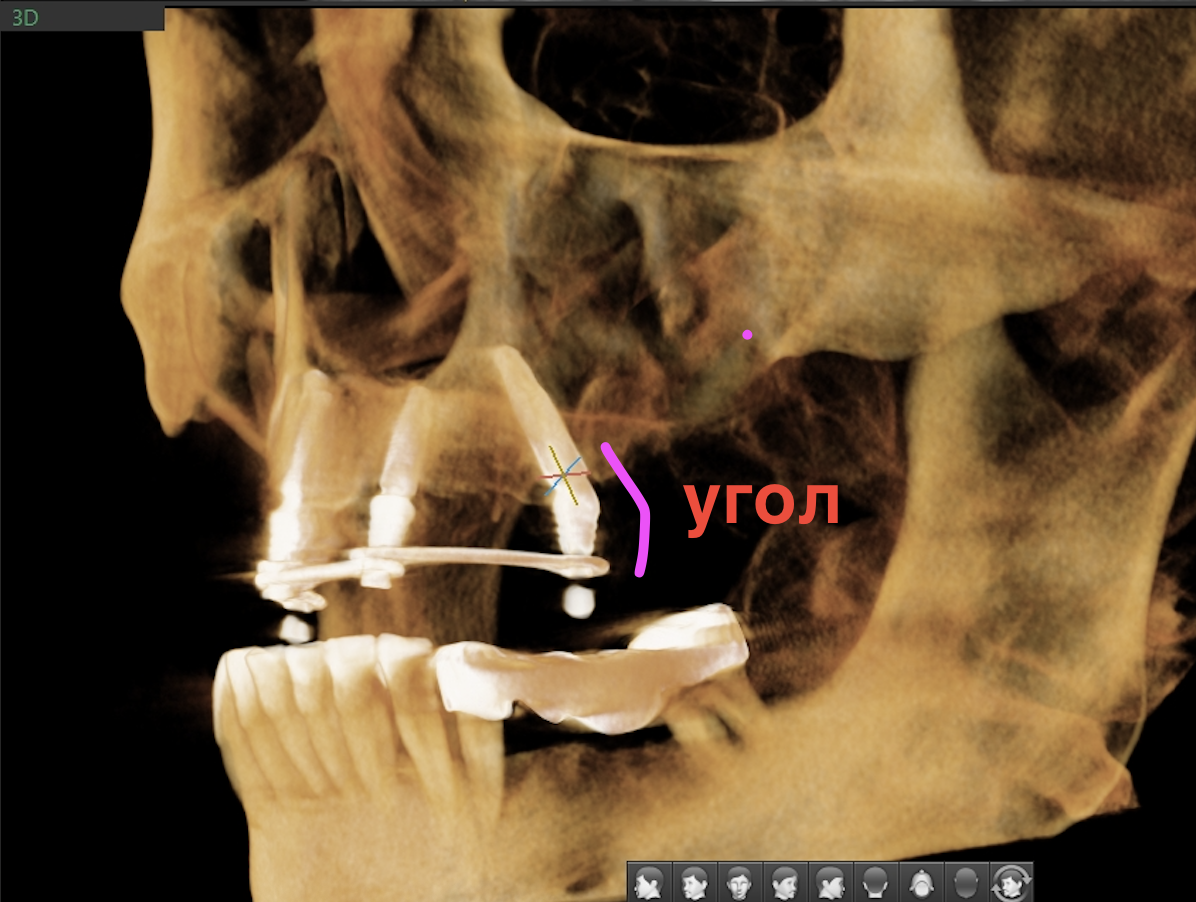

При четырёх опорах задние (дистальные) имплантаты ставятся под углом. Это принципиальный момент протокола.

"Всё-на-4", имплантат под углом, угловой мультиюнит